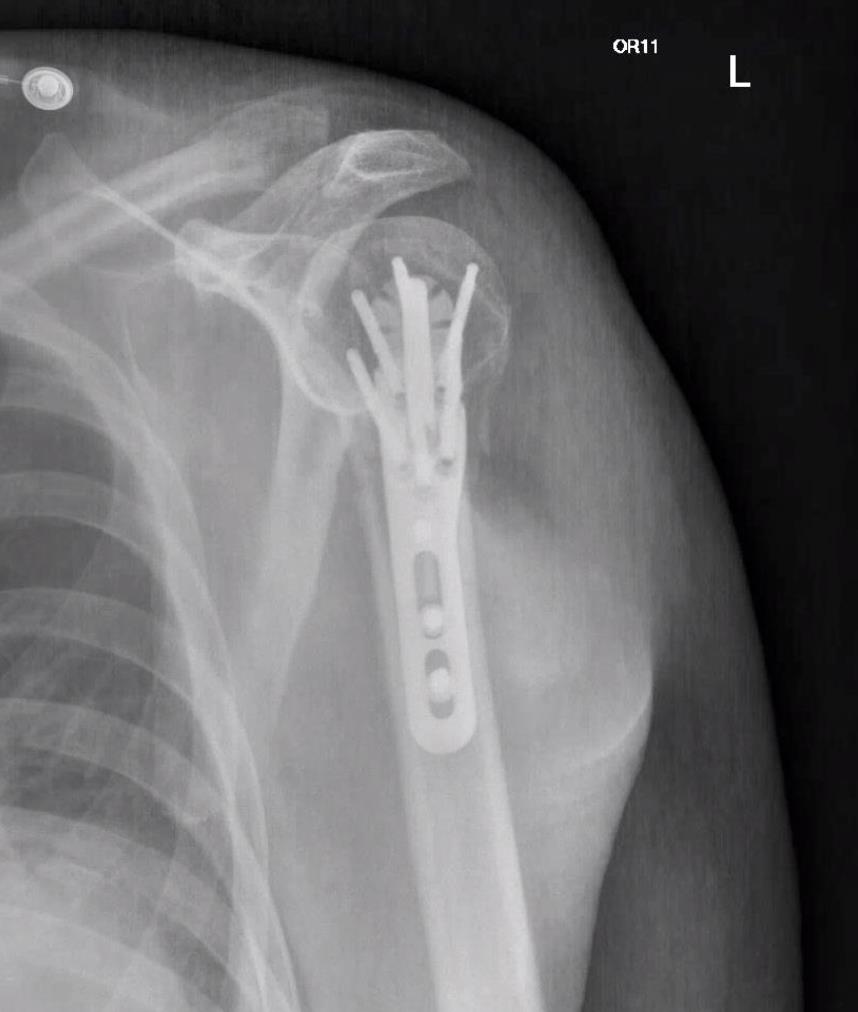

• The Proximal Humerus Fixation System (PHFS) from Skeletal Dynamics is a plate-and-peg/screw construct designed around proximal humeral anatomy for fixation of fractures, fracture-dislocations, osteotomies, and non-unions of the proximal humerus.

• The system centers on a proximal humerus plate with smooth locking pegs, locking/compression screws, and a central fixed-angle peg, with both straight and curved plate options.

• Distal shaft fixation

• Threaded 4.5 mm drill guides or soft-tissue protectors are placed into shaft slots or round holes.

• A 3.2 or 3.5 mm drill is advanced to the far cortex, and depth is measured with a gauge.

• FreeFix 4.5 mm compression screws are typically used in oblong slots to compress the plate to the bone and allow small translational adjustments.

• Once plate position is finalized, 4.5 mm FreeFix locking screws are inserted into round holes to provide fixed-angle diaphyseal support.

• Tuberosity fixation and closure

• Heavy nonabsorbable sutures are passed close to the rotator cuff tendon insertions on the tuberosities.

• These sutures are tied to side, front, or top-loading suture holes in the proximal plate or accessory suture plate to secure the tuberosities to the plate and reestablish the cuff footprint.

• Final fluoroscopy confirms reduction, peg and screw lengths, plate height relative to the greater tuberosity, and absence of joint penetration or subacromial impingement risk.